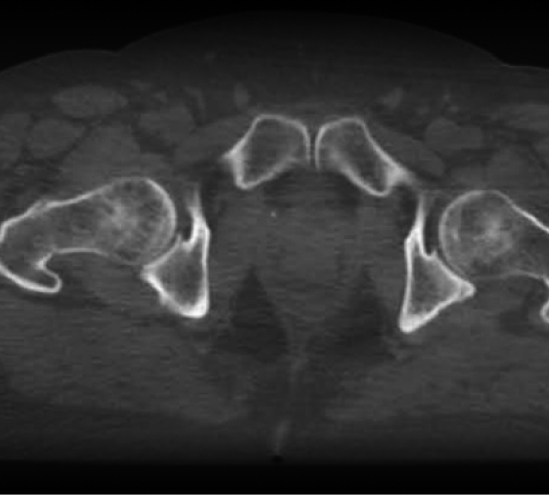

МОЖЛИВІСТЬ ПЕРИФЕРІЙНОГО ЛІКУВАННЯ

46 см бічного зсуву

Повне лікування молочної залози Тангенціальні пухлини

Повне лікування молочної залози

3. Більше отвір / Ефективно лікує периферійні пухлини